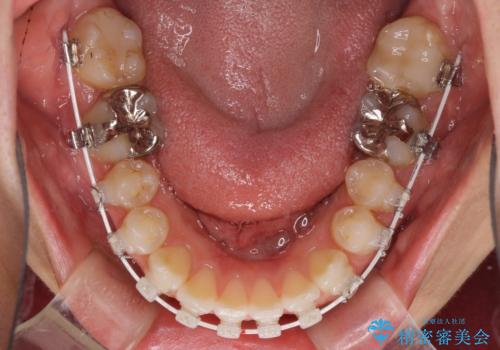

- 矯正装置

- 審美装置

上顎歯列が、下顎に対して前方にありましたが、口元に出っ歯の印象がなかったため、親知らずを抜歯した上で、上顎歯列全体を後方に移動させることとしました。

咬合力が強いため、アンカースクリューを使用し、ワイヤー装置にて矯正治療を行うこととしました。